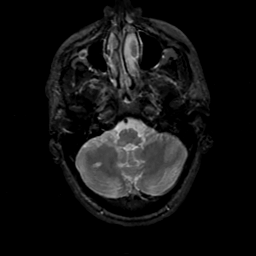

MR Study #17, July 7, 1991 -- Slice #9

[Home][Help][Clinical][Tour 1][Tour 2] Slice 9